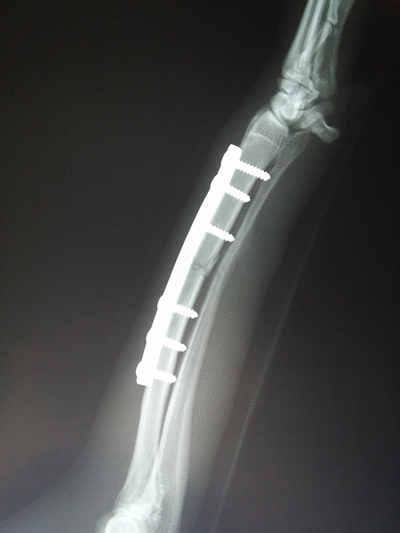

Рентгенография — исследование внутренней структуры объектов, которые проецируются при помощи рентгеновских лучей на специальную плёнку, бумагу или другой носитель. Наиболее часто термин относится к медицинскому неинвазивному исследованию, основанному на получении суммационного проекционного изображения анатомических структур организма посредством прохождения через них рентгеновских лучей и регистрации степени ослабления рентгеновского излучения.

При помощи рентгена можно исследовать патологии грудной полости (сердце, легкие, пищевод), брюшной полости кишечник, печень мочевой пузырь и другие органы, опорно-двигательный аппарат. Ценную информацию предоставляют нам снимки с введением рентгеноконтрастного вещества (ангиография, миелография).